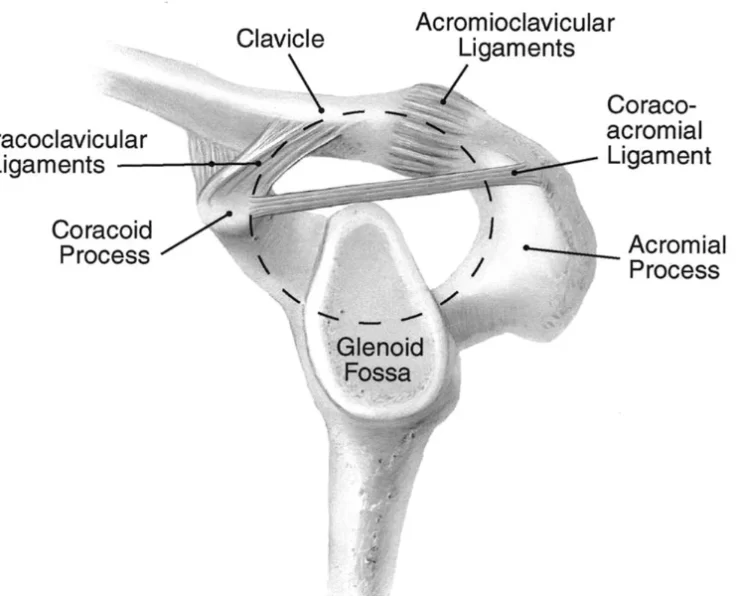

AC Joint Reconstruction

The acromioclavicular joint, often known as the AC joint, is positioned on the top of the shoulder, where the clavicle (collarbone) meets the acromion (shoulder…

AC Joint Excision

The goal of the procedure is to remove the uncomfortable and injured Acromioclavicular Joint (ACJ) without causing it to become unstable.